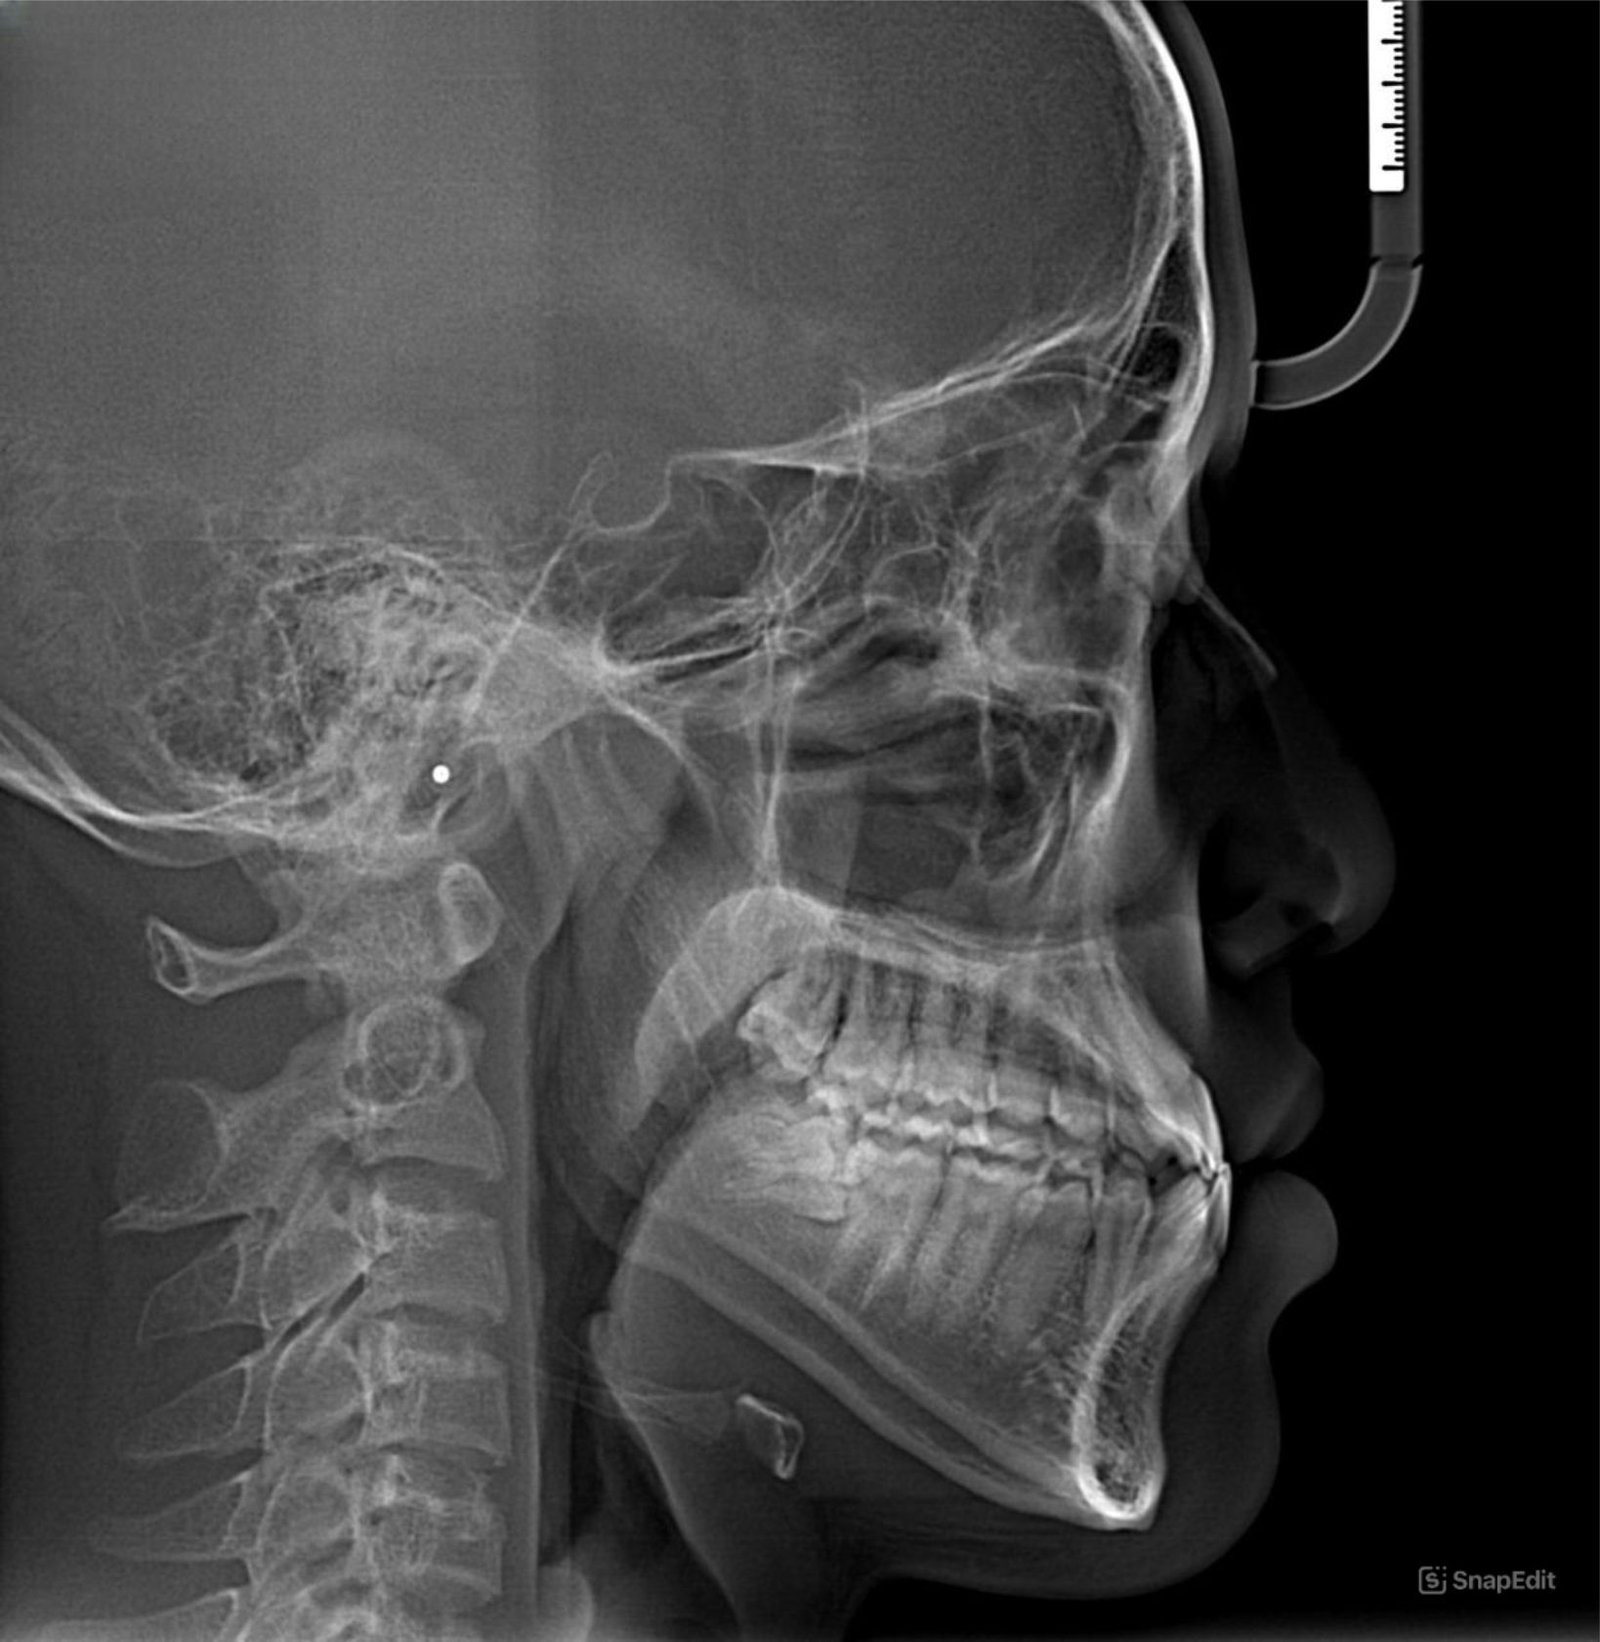

Rontgen Lateral Cepalomatric ini menunjukkan pertumbuhan dan perkembangan hubungan kepala, rahang, dan gigi dari penampakan samping.